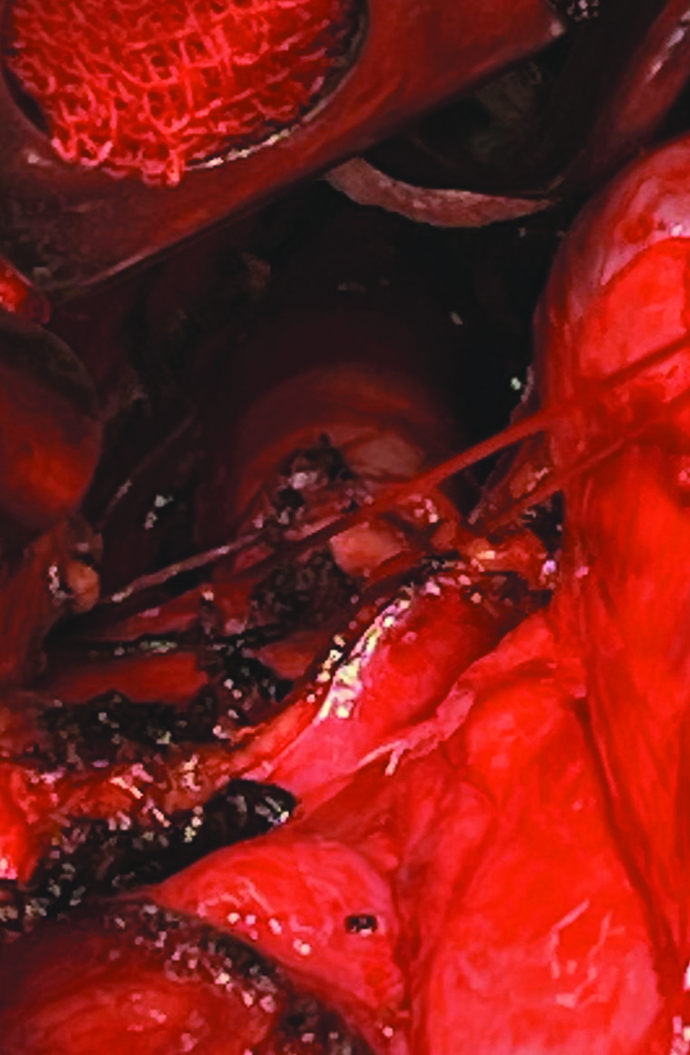

The tissue of the right lung is placed in its ‘proper’ hemithorax, and the mesh implant is placed above the hernia gate and attached with single interrupted sutures (Fig. 6).

Figure 6. Installation of a mesh implant on the right intrapleurally on the right: stitching with dacron threads to the sternum when access is closed.